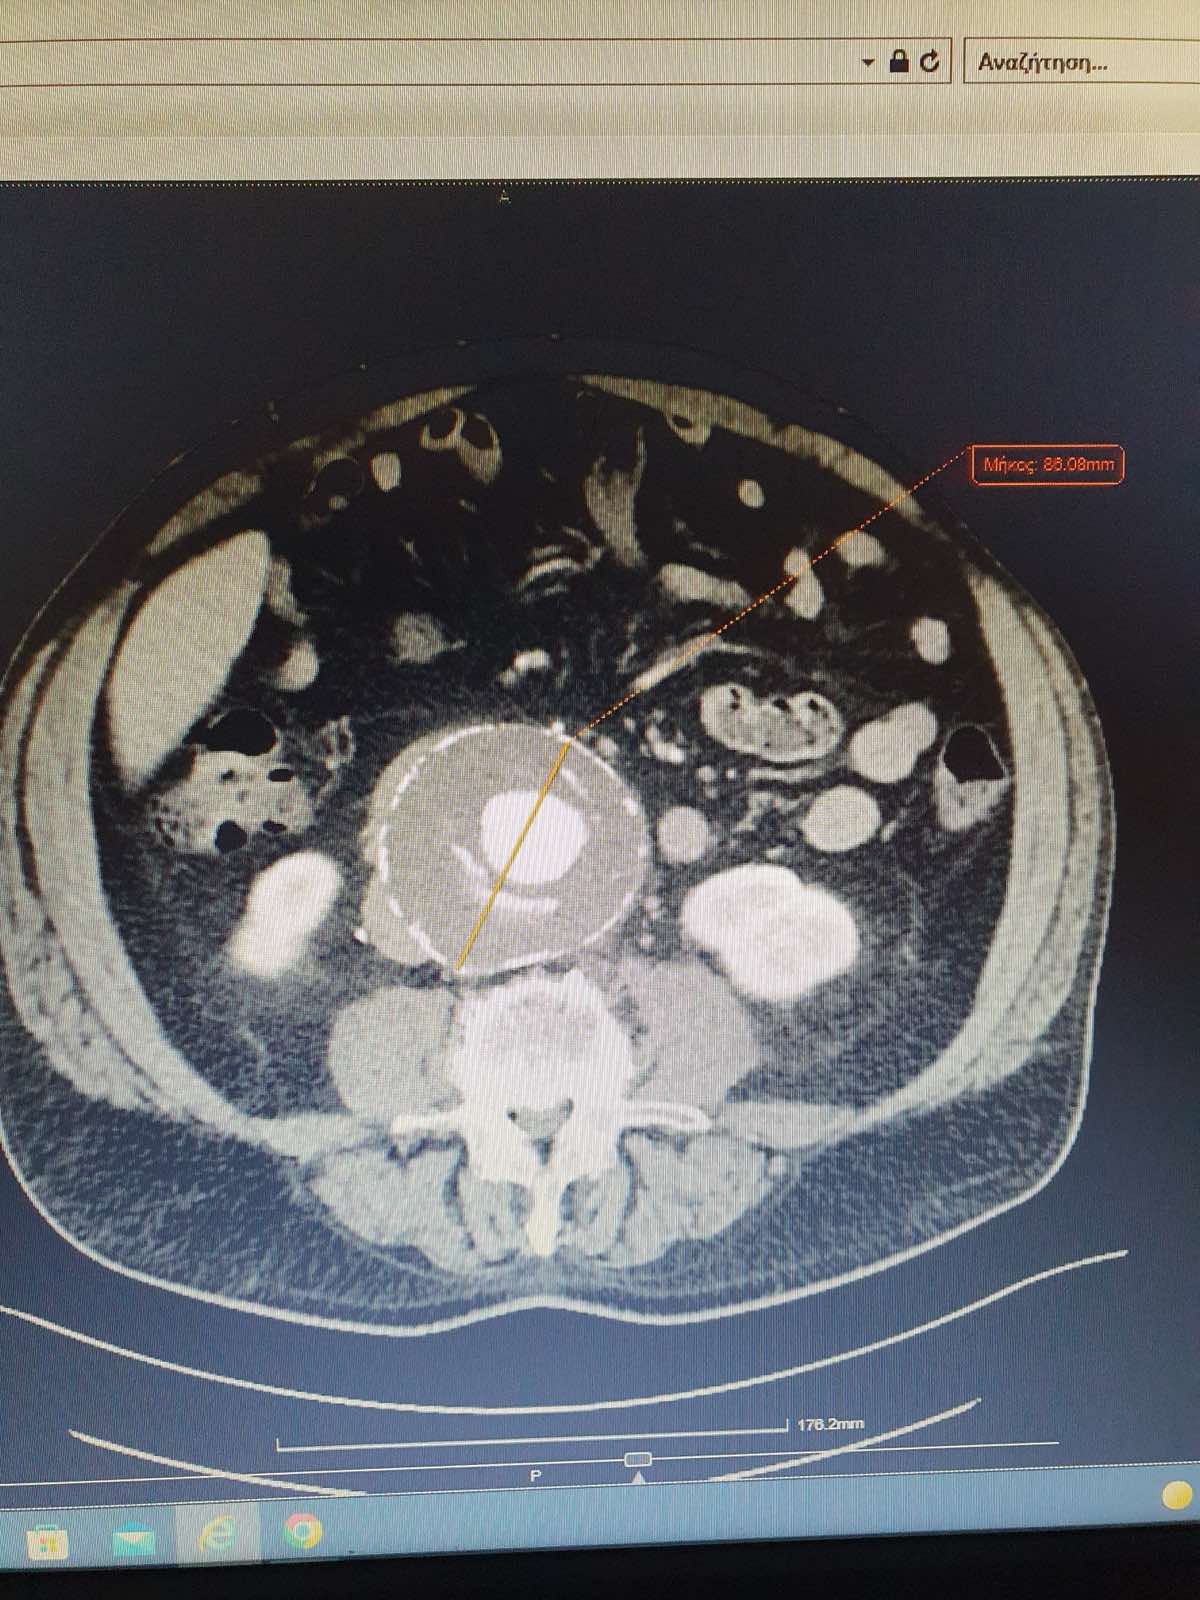

Η διάγνωση του ανευρύσματος κοιλιακής αορτής γίνεται με triplex κοιλιακής αορτής ή αξονική τομογραφία κοιλίας. Κάθε άνθρωπος (στο πλείστο των περιπτώσεων άνδρας) που υπερβαίνει το 60ο έτος της ηλικίας του πρέπει να ελέγχεται με triplex κοιλιακής αορτής (εάν έχει 1ου βαθμού συγγενή με ανεύρυσμα κοιλιακής αορτής η εξέταση πρέπει να γίνει μετά το 50ο έτος). Σε ασθενείς που χρειάζονται αποκατάσταση του ανευρύσματος κοιλιακής αορτής η πιο λεπτομερή προεγχειρητική εξέταση είναι η αξονική αγγειογραφία κοιλιακής αορτής και λαγονίων. Σε ασθενείς που δεν μπορούν να υποβληθούν σε αξονική αγγειογραφία διενεργείται μαγνητική αγγειογραφία κοιλιακής αορτής και λαγονίων.